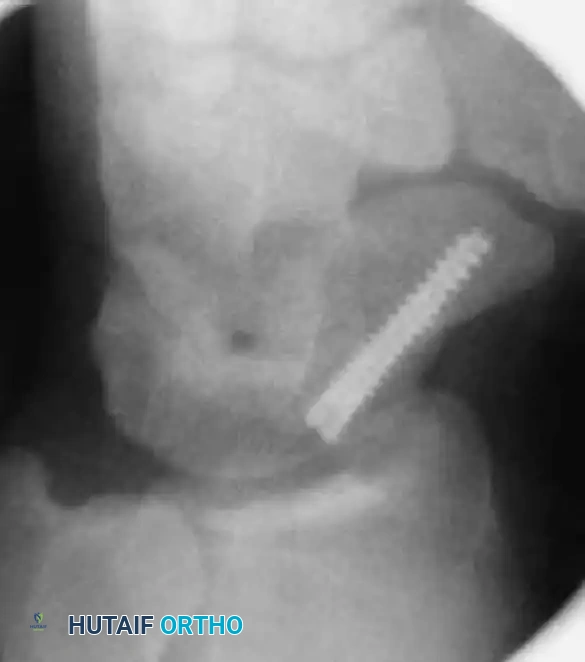

6. Screw Insertion and Countersinking

• Select the appropriate headless compression screw (e.g., Acutrak), ensuring it is 4 mm shorter than the measured scaphoid length.

• Advance the screw over the guidewire using the cannulated screwdriver.

• Monitor the insertion under fluoroscopy. The variable pitch of the headless screw will compress the fracture site as it is advanced.

• Drive the screw until the trailing edge is buried 1 to 2 mm beneath the proximal articular cartilage, and the leading edge is 1 to 2 mm short of the distal cortex.

Screw Insertion A

Screw Insertion B

Screw Insertion C

FIGURE: (A) Joysticks and anti-rotation wires are maintained during dorsal implantation of the screw. (B, C) Final fluoroscopy confirms the precise placement and countersinking of the headless compression screw.

• Remove the guidewire, anti-rotation wires, and joysticks. Obtain final multi-planar fluoroscopic images to verify fracture compression, anatomic reduction, and complete intraosseous screw containment.